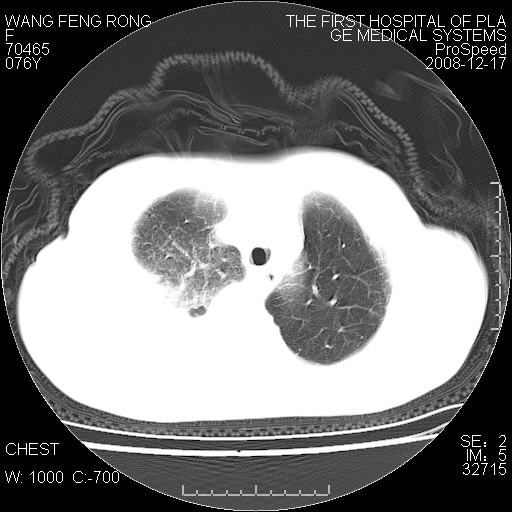

右侧胸腔积液,致右肺膨胀不全,双肺间质纤维化改变

1)考虑两肺炎症感染;不排除肺泡癌可能。2)两肺间质纤维化。3)右侧胸腔积液。

右侧胸腔积液,右肺膨胀不全伴感染(不除外肺癌),双肺间质水肿

结核(干酪性肺炎、支气管内膜结核、结核性胸水、淋巴结肿大钙化)

右肺大部实变,其内可见支气管影,但分支减少,宽窄不均,走行僵直,同侧胸腔大量积液;纵隔内见多发淋巴结影,但淋巴结大部有钙化;主动脉壁钙化;临床上病人咳嗽、消瘦。所以我考虑:1、结核(依据:右下肺实变,纵隔内淋巴结符合结核表现,同侧并发胸膜炎表现);2、支气管肺泡癌(依据:实变的肺组织内支气管分支减少,宽窄不均,走行僵直,没有把它放在第一诊断是因为没有看到明显肿大的淋巴结);3、动脉硬化(主动脉壁钙化就支持这个诊断)。

病理结果,肺泡癌